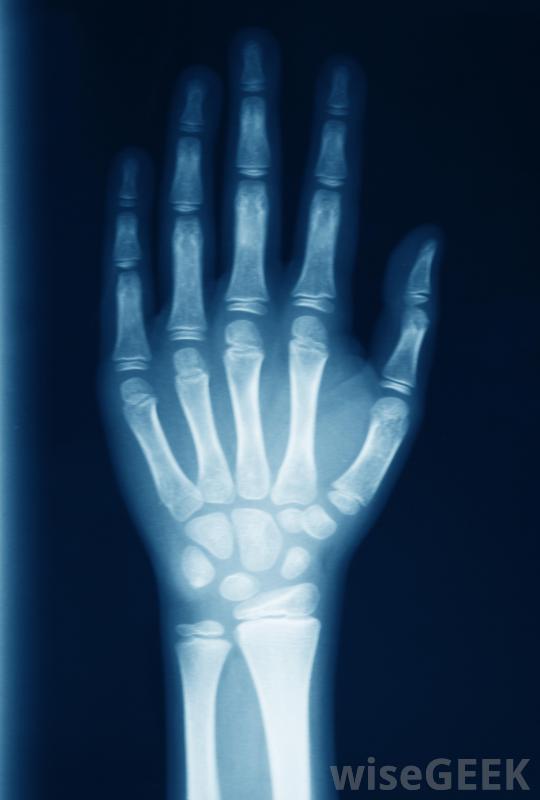

医生可能会要求腕关节核磁共振来评估最近有外伤或关节不稳定症状的病人。要求做腕关节核磁共振的另一个原因是如果其他影像学检查发现异常,像x射线或计算机断层扫描这些可能是在外伤后,如疑似骨折。如果它们显示出难以准确诊断的问题迹象,医生可能会要求核磁共振成像以获得更详细的信息。这些附加信息有助于诊断,并可能使医生制定更有效和更合适的治疗计划

如果怀疑骨折,可以接受手腕MRI检查。

手腕MRI可以帮助诊断手腕疼痛的原因。